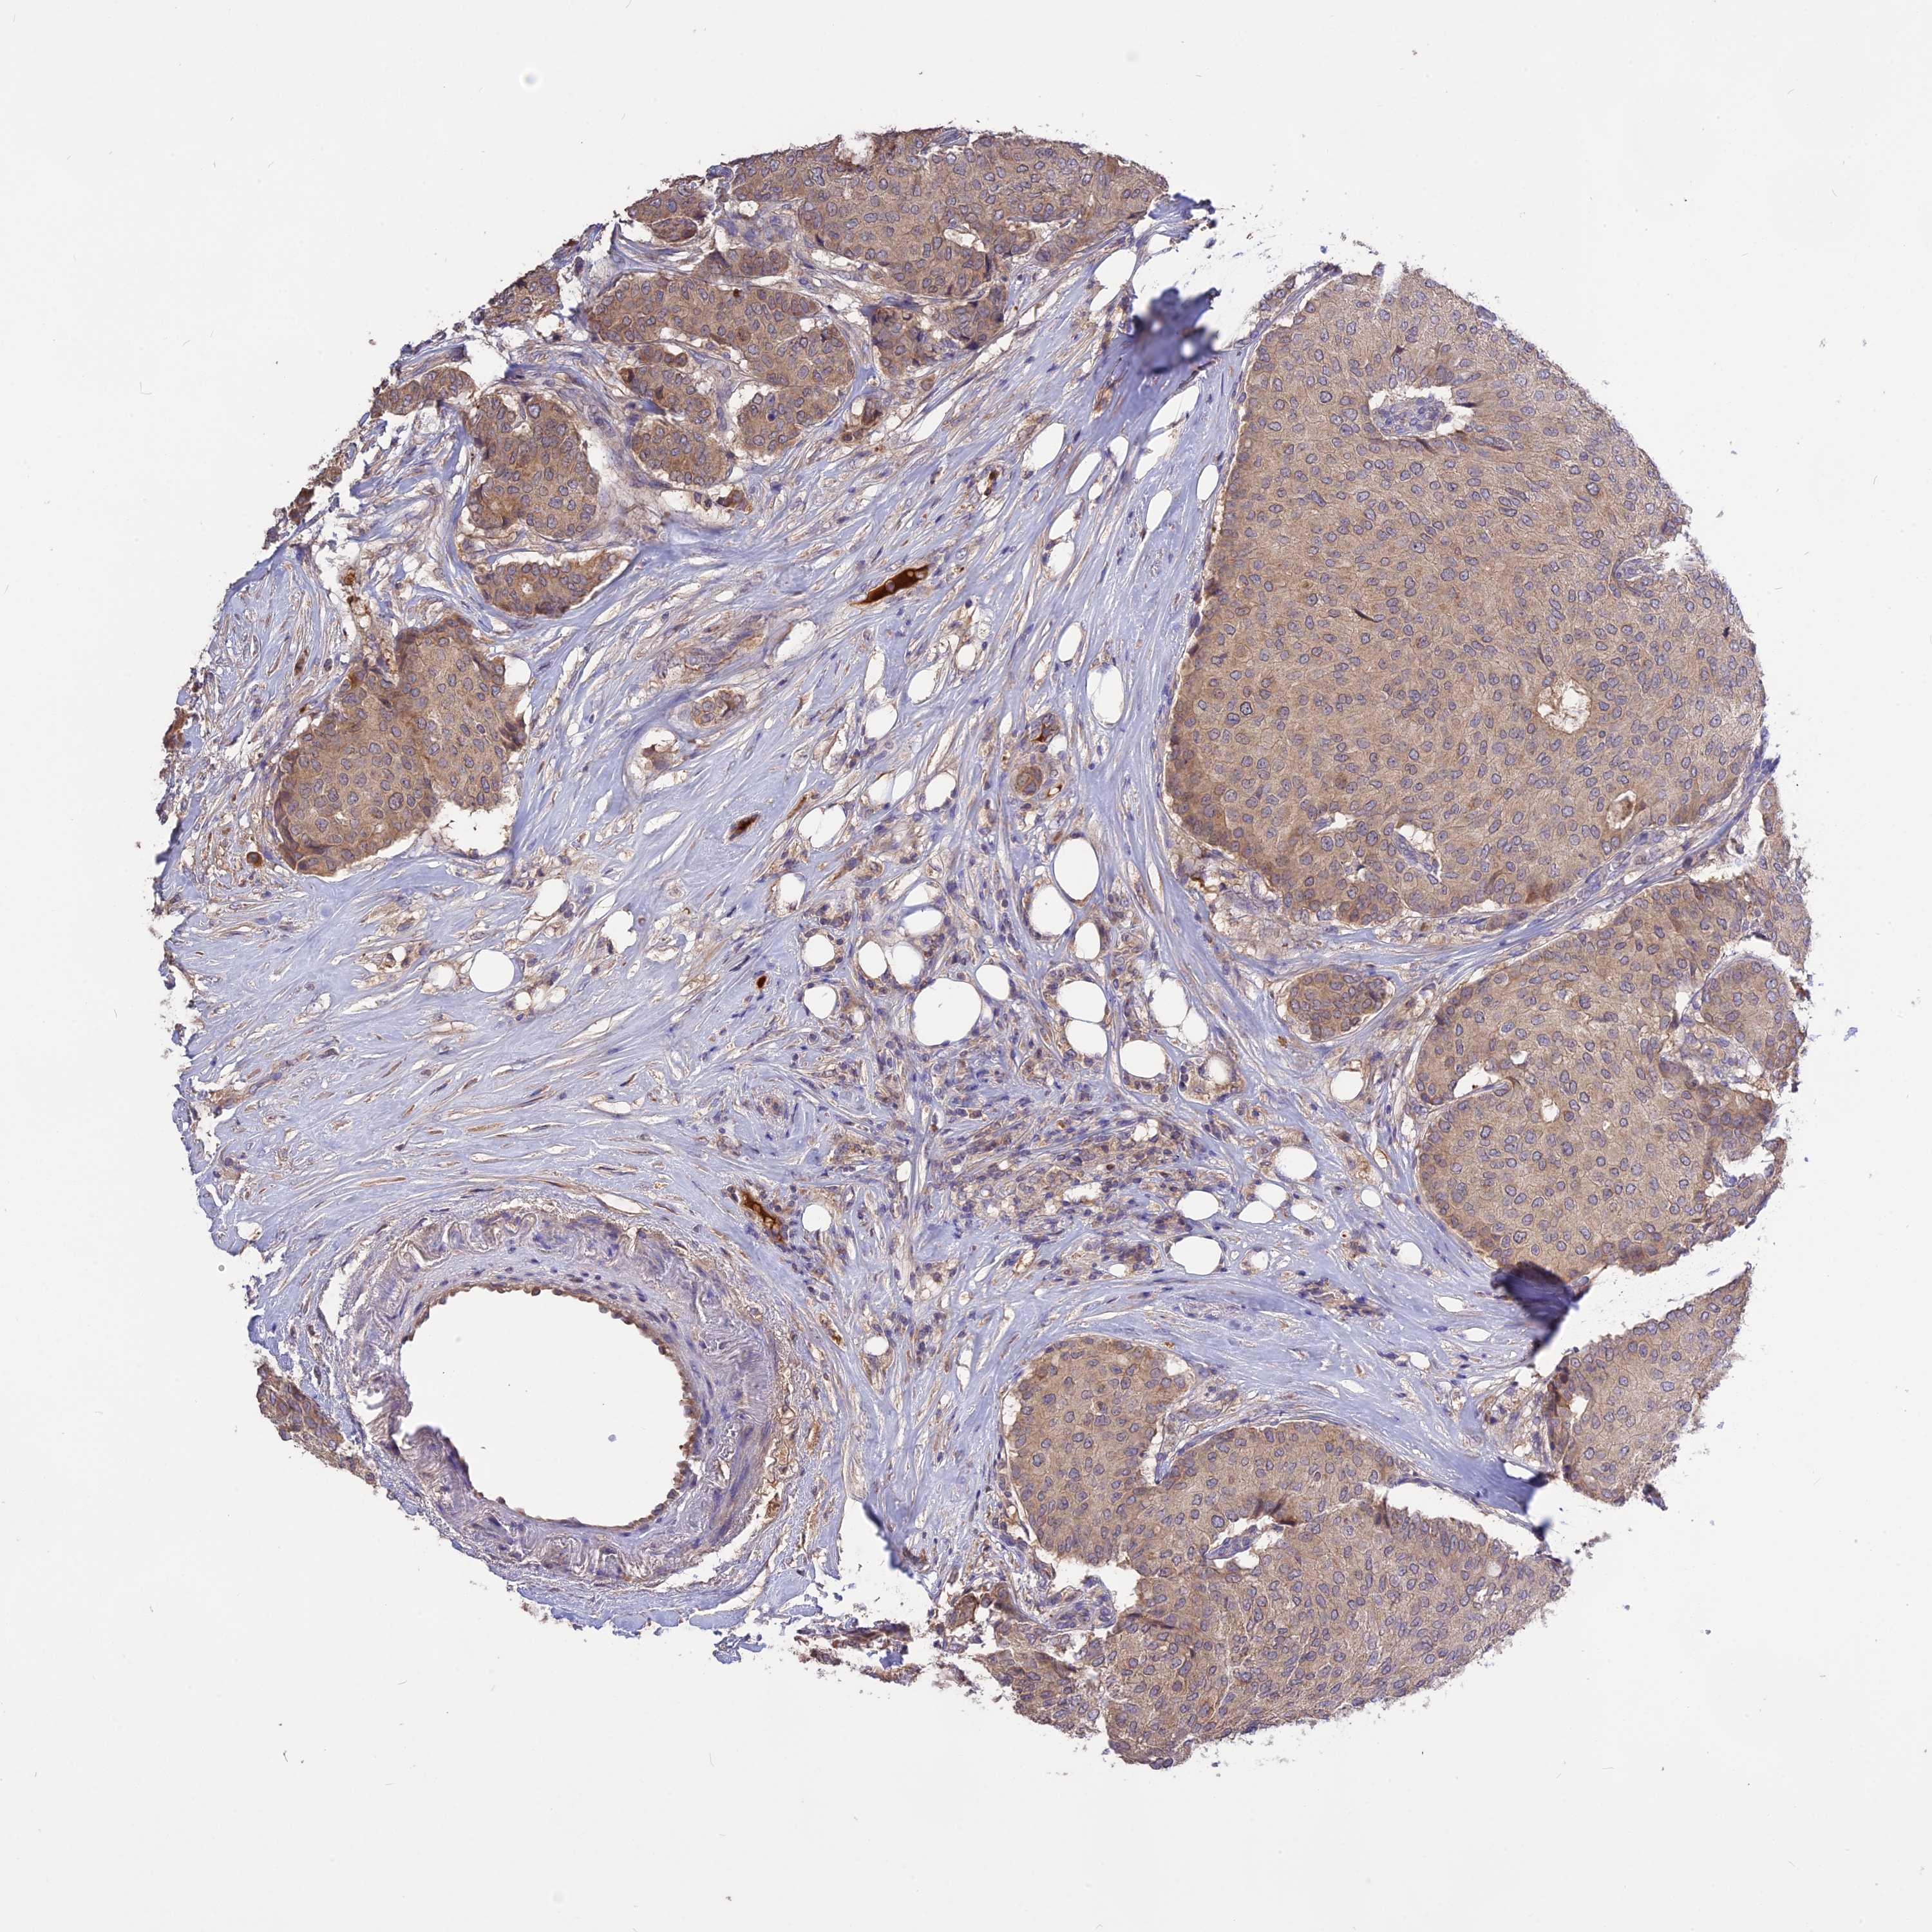

CANCER BREAST CANCER Show tissue menu

BRCA TCGA BRCA VALIDATION PROTEIN EXPRESSION

Breast cancer

Human cancer